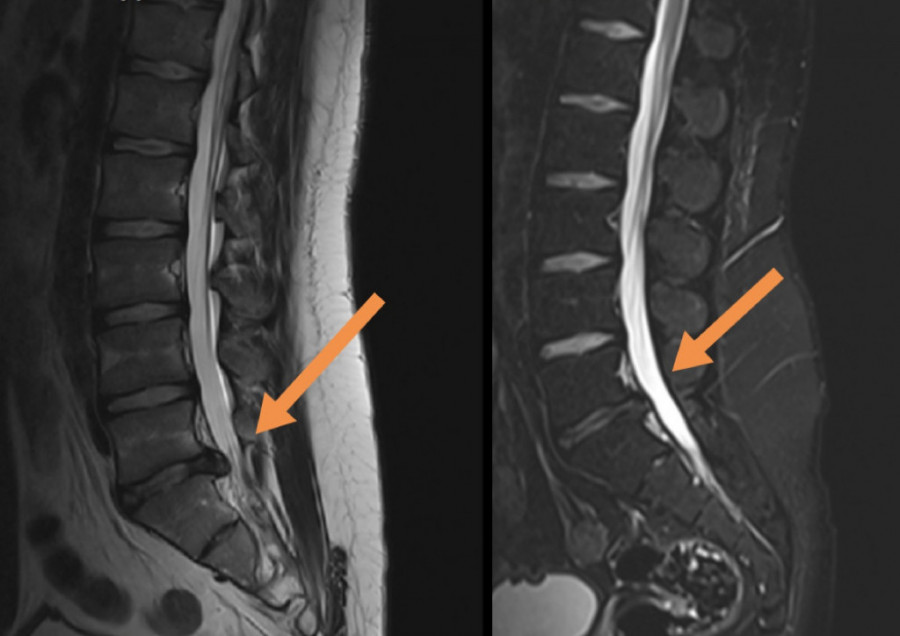

Dekompresijski tretman kičme ili DTK je jedini neoperativni tretman, kompjuterski kontrolisan i dijagnostički povezan, koji postiže odlične rezultate kod teških slučajeva diskus hernije, degenerativnih promena, artritisa, stenoze spinalnog kanala i pritiska na nervne korenove. Dekompresiona terapija kičme deluje tako da putem cikličnih faza distrakcije i relaksacije i pravilnom pozicioniranjem diska dovodi do povećanja međupršljenskog prostora za nekoliko milimetara (1-2), oslobađa živce - između njih, smanjuje bol, trnjenje, glavobolje, vrtoglavice, kao i slabosti u šakama i stopalima. Ovaj tretman stvara negativan pritisak i efekat vakuma u samom diskusu koji se nalazi između dva pršljena i na taj način povlači herniju unutar diska. Vakum povećava cirkulaciju oko diska i tako leči upalni proces. Dekompresijski tretman vrši istezanje receptora u mišićima i ligamentima oko kičmenog stuba, smanjuje pritisak na međupršljenske zglobove povećavajući pokretljivost kičme. Zatim odvaja, odnosno vrši separaciju pršljenova i povećava prostor između njih, proširenje intravertebralnog foramena i ispravljanje krivina kičmenog stuba. Klinički je dokazana efikasnost ove primene od 85 odsto.